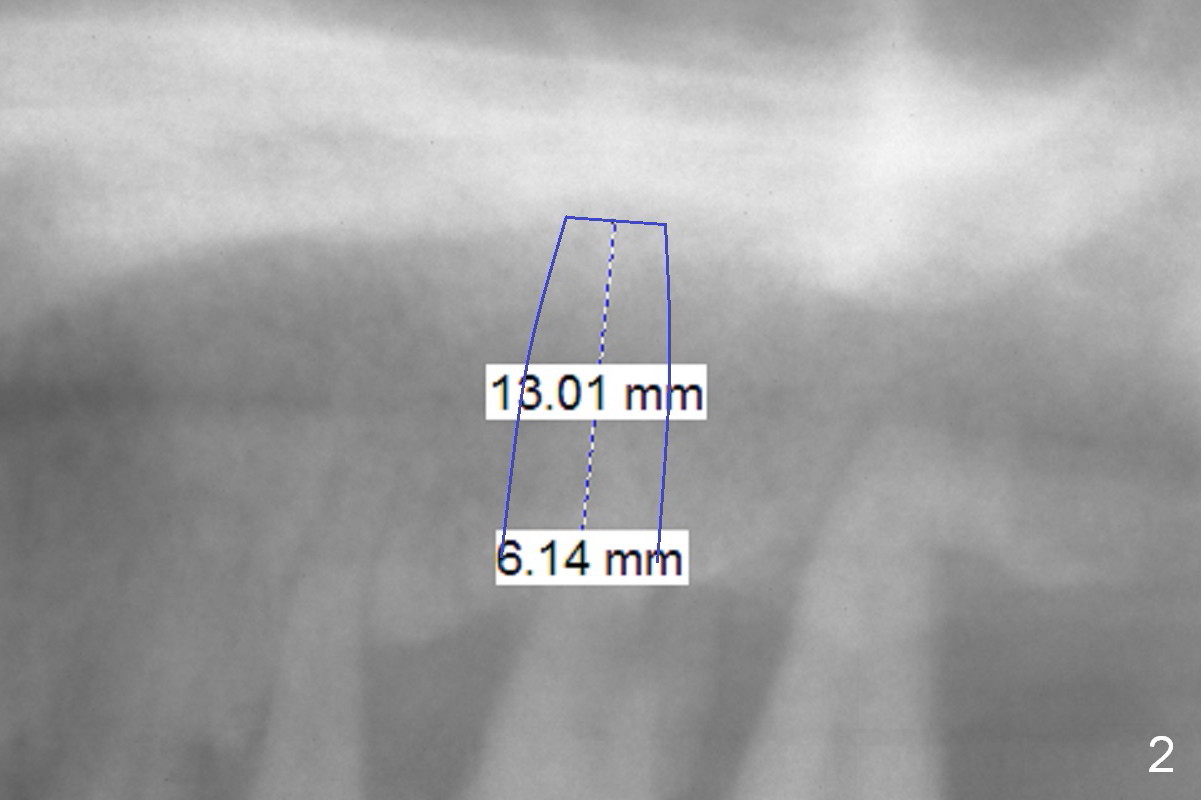

The teeth #14 and 18 of a 46-year-old man become symptomatic 1 month after #4 implant placement. While the socket at #14 is shallow, the apical bone is abundant (Fig.1). The longest IBS implant should be safe (13 mm, Fig.2). In contrast, the socket at #18 is relatively deep, the apical bone is short (Fig.3). A shorter implant (11 mm or less, Fig.4) should be chosen. Osteotomy in the new bone should be 4 mm. Try in a 5x9 mm dummy implant at #18. No antibiotic is used for socket treatment. The bone density in the mandible should be high (drills), whereas that in the maxilla may be low (expanders) or medium (drills). Preop exam will decide which tooth needs treatment first. Take photos PRN.